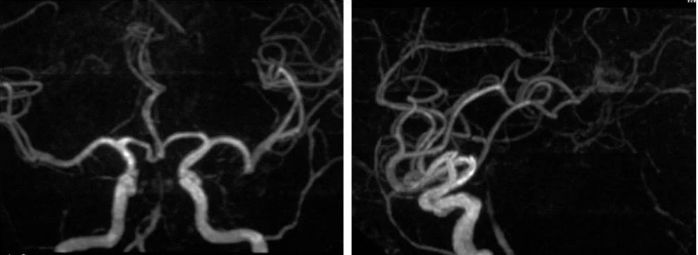

外院DSA:右椎动脉V4段次全闭塞,基底动脉有顺向显影,前向血流减慢;左椎动脉V3段闭塞,见基底动脉经脊髓前动脉代偿显影(图3,4)。

图3

图4